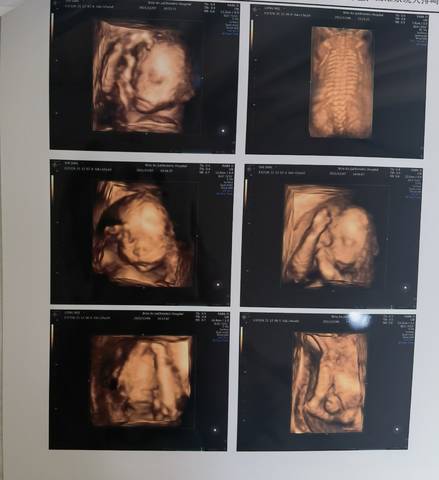

请帮忙看一下右下角最后一张图是哪个部位

你好,这个部位的话那是没办法去帮你判断的哪,一般的话应该都差不多的吧,你要多观察一下嘛。